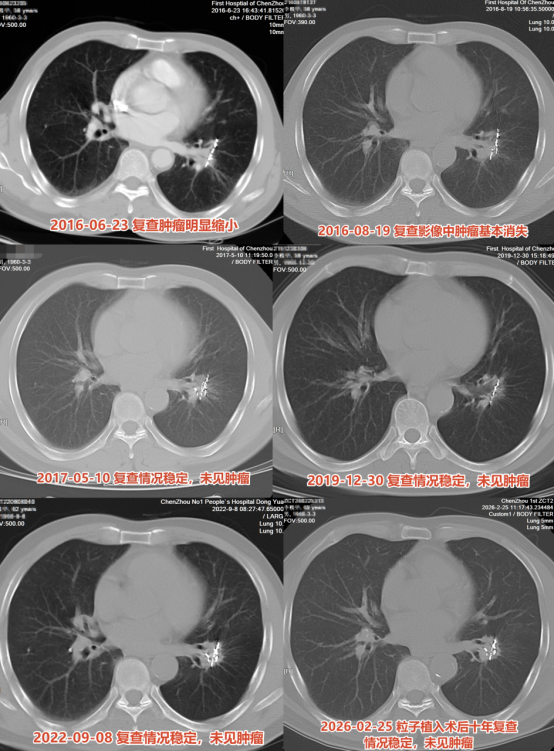

65岁爷爷患肺癌晚期存活10年 精准治疗创奇迹

65岁爷爷患肺癌晚期存活10年 精准治疗创奇迹。今年春天,65岁的李伯伯来到郴州市第一人民医院影像专家门诊进行肺癌治疗后的随访复查。十年前,他因咳嗽到医院就诊,CT报告显示左肺下叶恶性肿瘤并对侧肺叶内转移;随后住院完善检查及病理,最终诊断为左肺下叶肺鳞癌 T2N0M1 IV期。

但李伯伯的治疗团队没有拘泥于晚期肺癌的姑息治疗,而是根据他的经济条件和治疗意愿,召集多学科团队反复讨论后,制定了一套组合方案:CT引导下放射性粒子植入术,联合GP方案(吉西他滨+铂类)化疗。